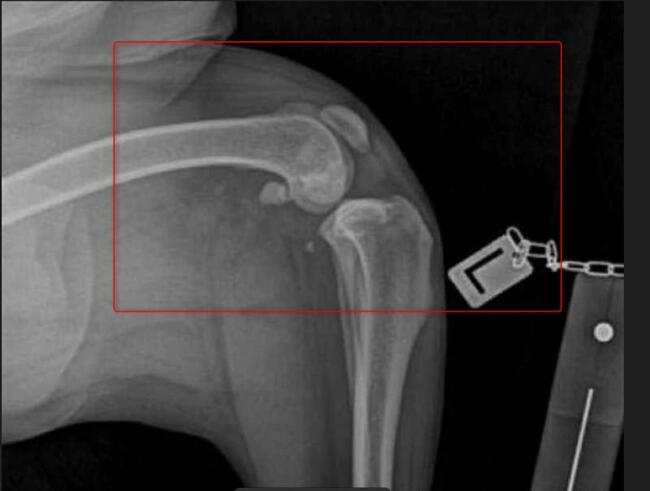

Mój ukochany Max ma dysplazje stawów tylne nogi oraz biodra odmawiają posłuszeństwa. Dotychczas starałam się finansować każdą wizytę, operację, zabiegi i rehabilitację. Niestety, nadszedł moment, gdy zostałam postawiona pod ścianą. Z osoby wspomagającej, mój przyjaciel i ja staliśmy się potrzebującymi.

Niestety stopień zwyrodnienia stawów i poziom zaawansowania choroby kwalifikuje Maxa na operację wstawienia endoprotez w obu biodrach, których koszt mimo moich oszczędności przekracza moje możliwości